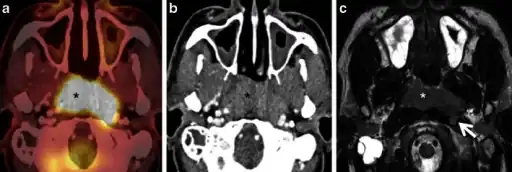

a) Axial PET/CT image reveals a FDG-avid mass in the nasopharynx in keeping with a known nasopharyngeal carcinoma b)axial CECT image shows the infiltrative nasopharyngeal carcinoma c) axial T2W MR image demonstrates the infiltrative nasopharyngeal carcinoma -